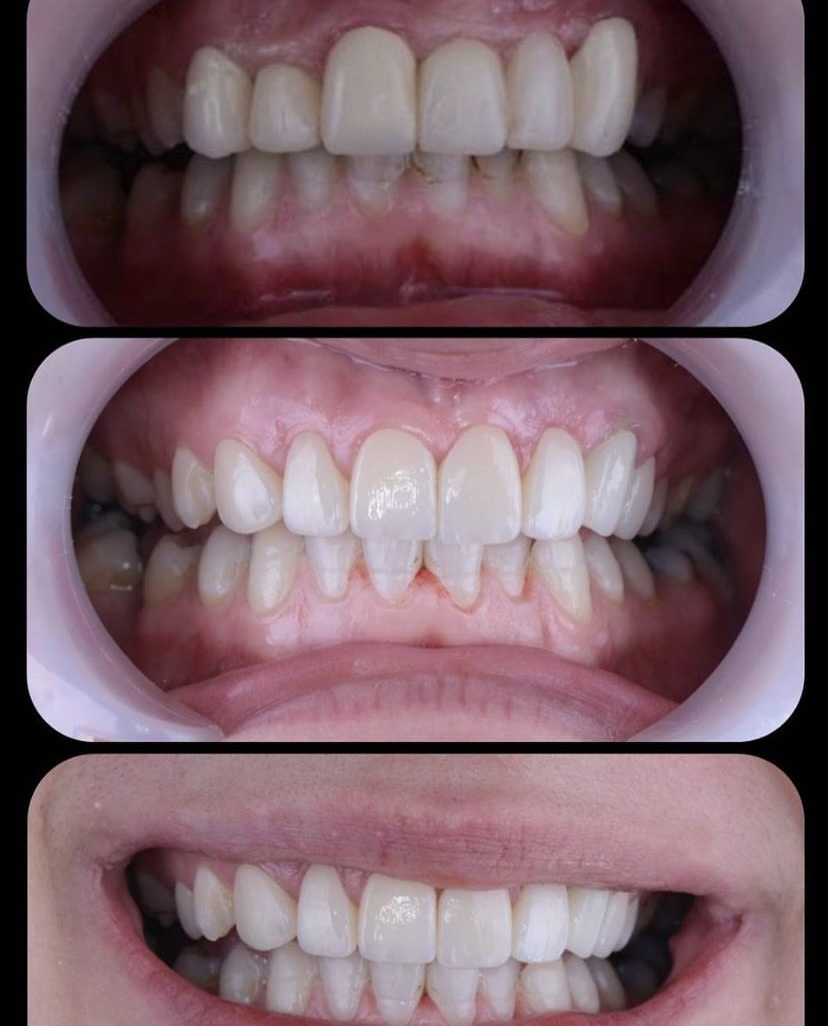

Öncesi̇-Sonrası Resi̇mler

Galeri Öncesi̇-Sonrası Resi̇mler